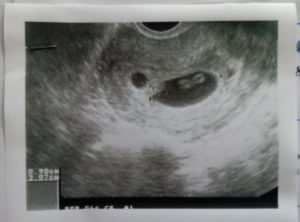

В исследованиях главным показателем является средний и внутренний диаметр плодного яйца (СВД). О сроке беременности судят по размеру имеющегося плодного яйца, которое в первые недели должно быть овальной или сферической формы. Это норма.

В норме форма может быть круглой или овальной. Но иногда УЗИ показывает вытянутость яйца. Обычно речь идет о гипертонусе матки, который требует лечения в стационаре. Яйцо вытянутой формы наблюдается при двойне и это не свидетельствует о патологии, это норма.

Самый распространенный диагноз, выявляемый УЗИ, — деформированное плодное яйцо, причины которого мы постараемся разобрать. По сути, этот диагноз — следствие постоянного тонуса матки, а это является угрозой для развития малыша.

Довольно часто после результатов УЗИ ставится диагноз «деформированное плодное яйцо», причины которого заключаются в повышенном тонусе матки. Практически каждая мама воспринимает такую новость, как приговор, и начинает ждать только самого худшего. Но это не правильно. Такой диагноз не означает, что у малыша нет шансов выжить и вырасти здоровым человеком.

Данное явление является патологией и чаще всего свидетельствует о неправильном развитии плода. В норме яйцо должно иметь овальную или круглую форму. Если оно сплюснуто по бокам, то это — первый признак гипертонуса матки. Пациентке нужно находиться под наблюдением врача какое-то время. Если в дальнейшем не развивается какая-либо опасная симптоматика, то угроза исключается.